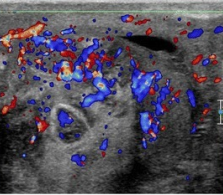

Epididymitis

- Enlarge epididymis

- Increased epididymal blood flow

- Normal testicular appearance